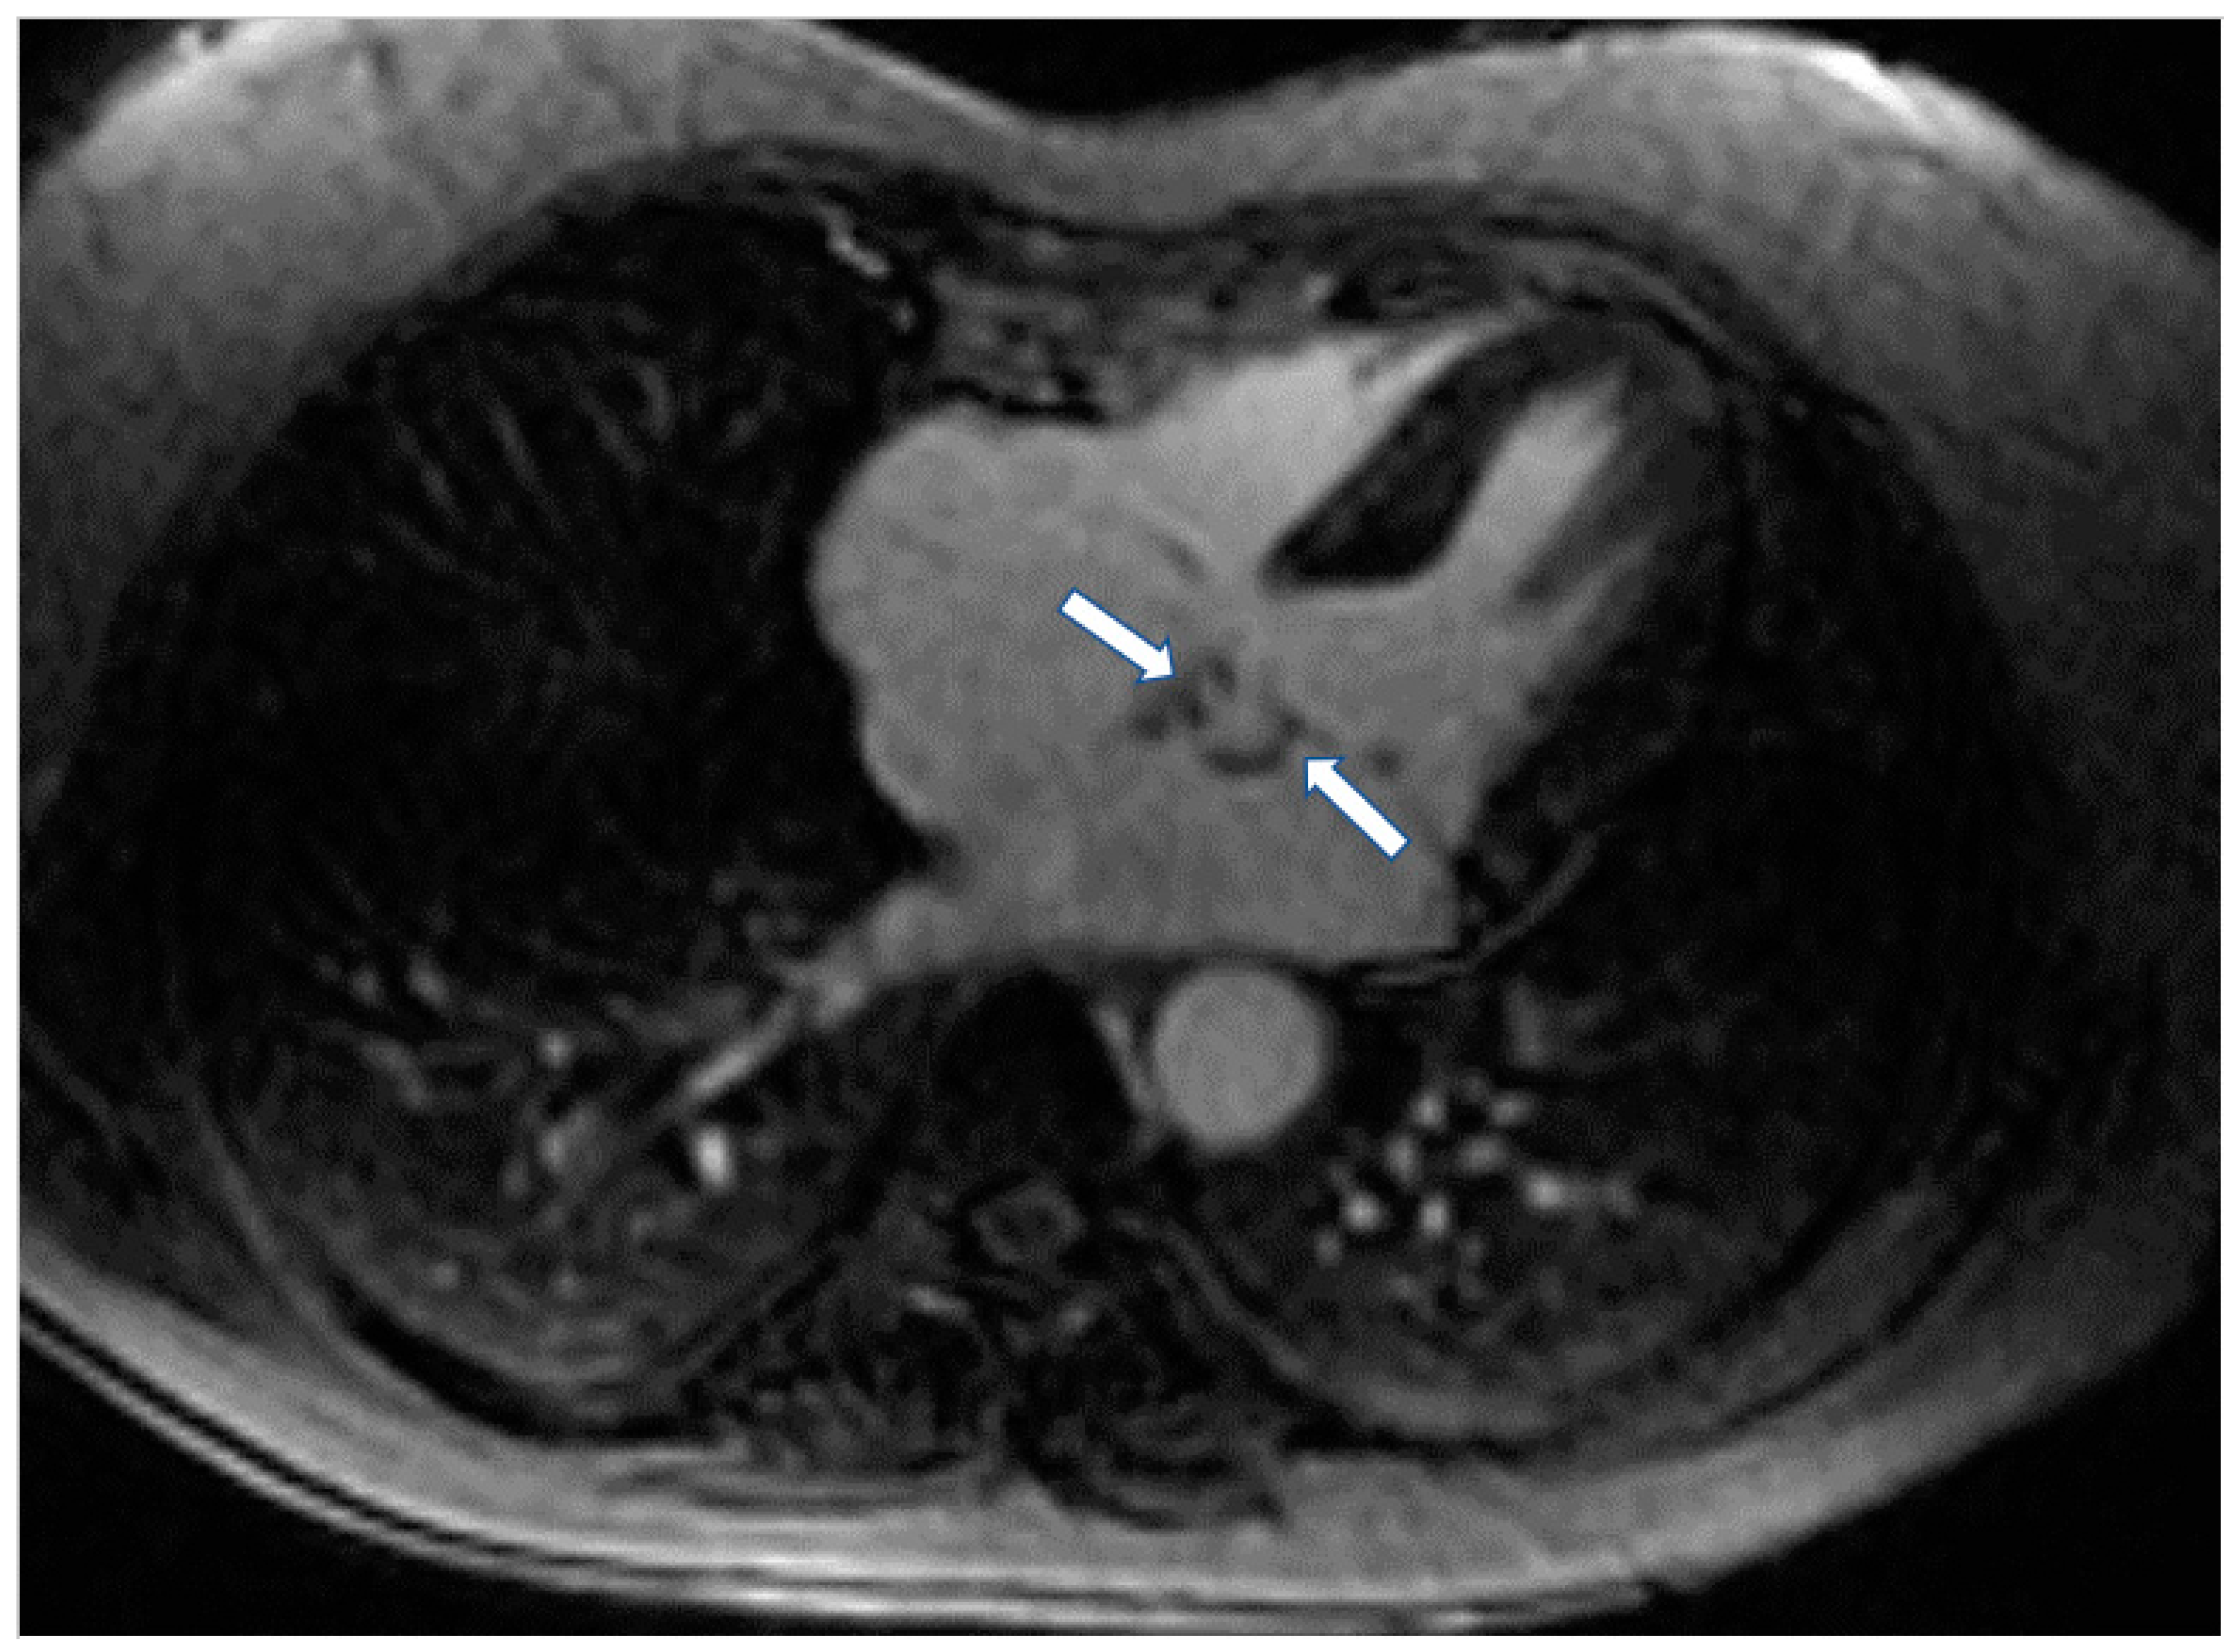

The high spatial resolution of CMR, in parallel with tissue characterization, helps to assess tissue invasion and differentiate potential etiologies. Mass localization is performed with dark- and white-blood imaging, followed by tissue characterization based on T1- and T2-weighted imaging, fat, and water suppression sequences, first-pass perfusion, early (EGE) and LGE (Figure 6) [95].

Figure 6.

Four chamber inversion recovery image showing the presence of fibroma (arrows) in left atrium.

CMR is also of value in the detection of intracardiac thrombi. Usually, the majority of thrombi is small, homogeneous, often associated with venous catheters and typically hypointense on first-pass perfusion, due to lack of vasculature [96]. Compared to thrombi, malignant tumors tend to be larger with first-pass perfusion abnormalities and LGE [96,97]. Parametric mapping has also demonstrated important diagnostic value (Figure 7) [97].

Figure 7.

Four chamber T1 mapping showing LV infiltration and RV-Right atrium masses (arrows) due to melanoma.